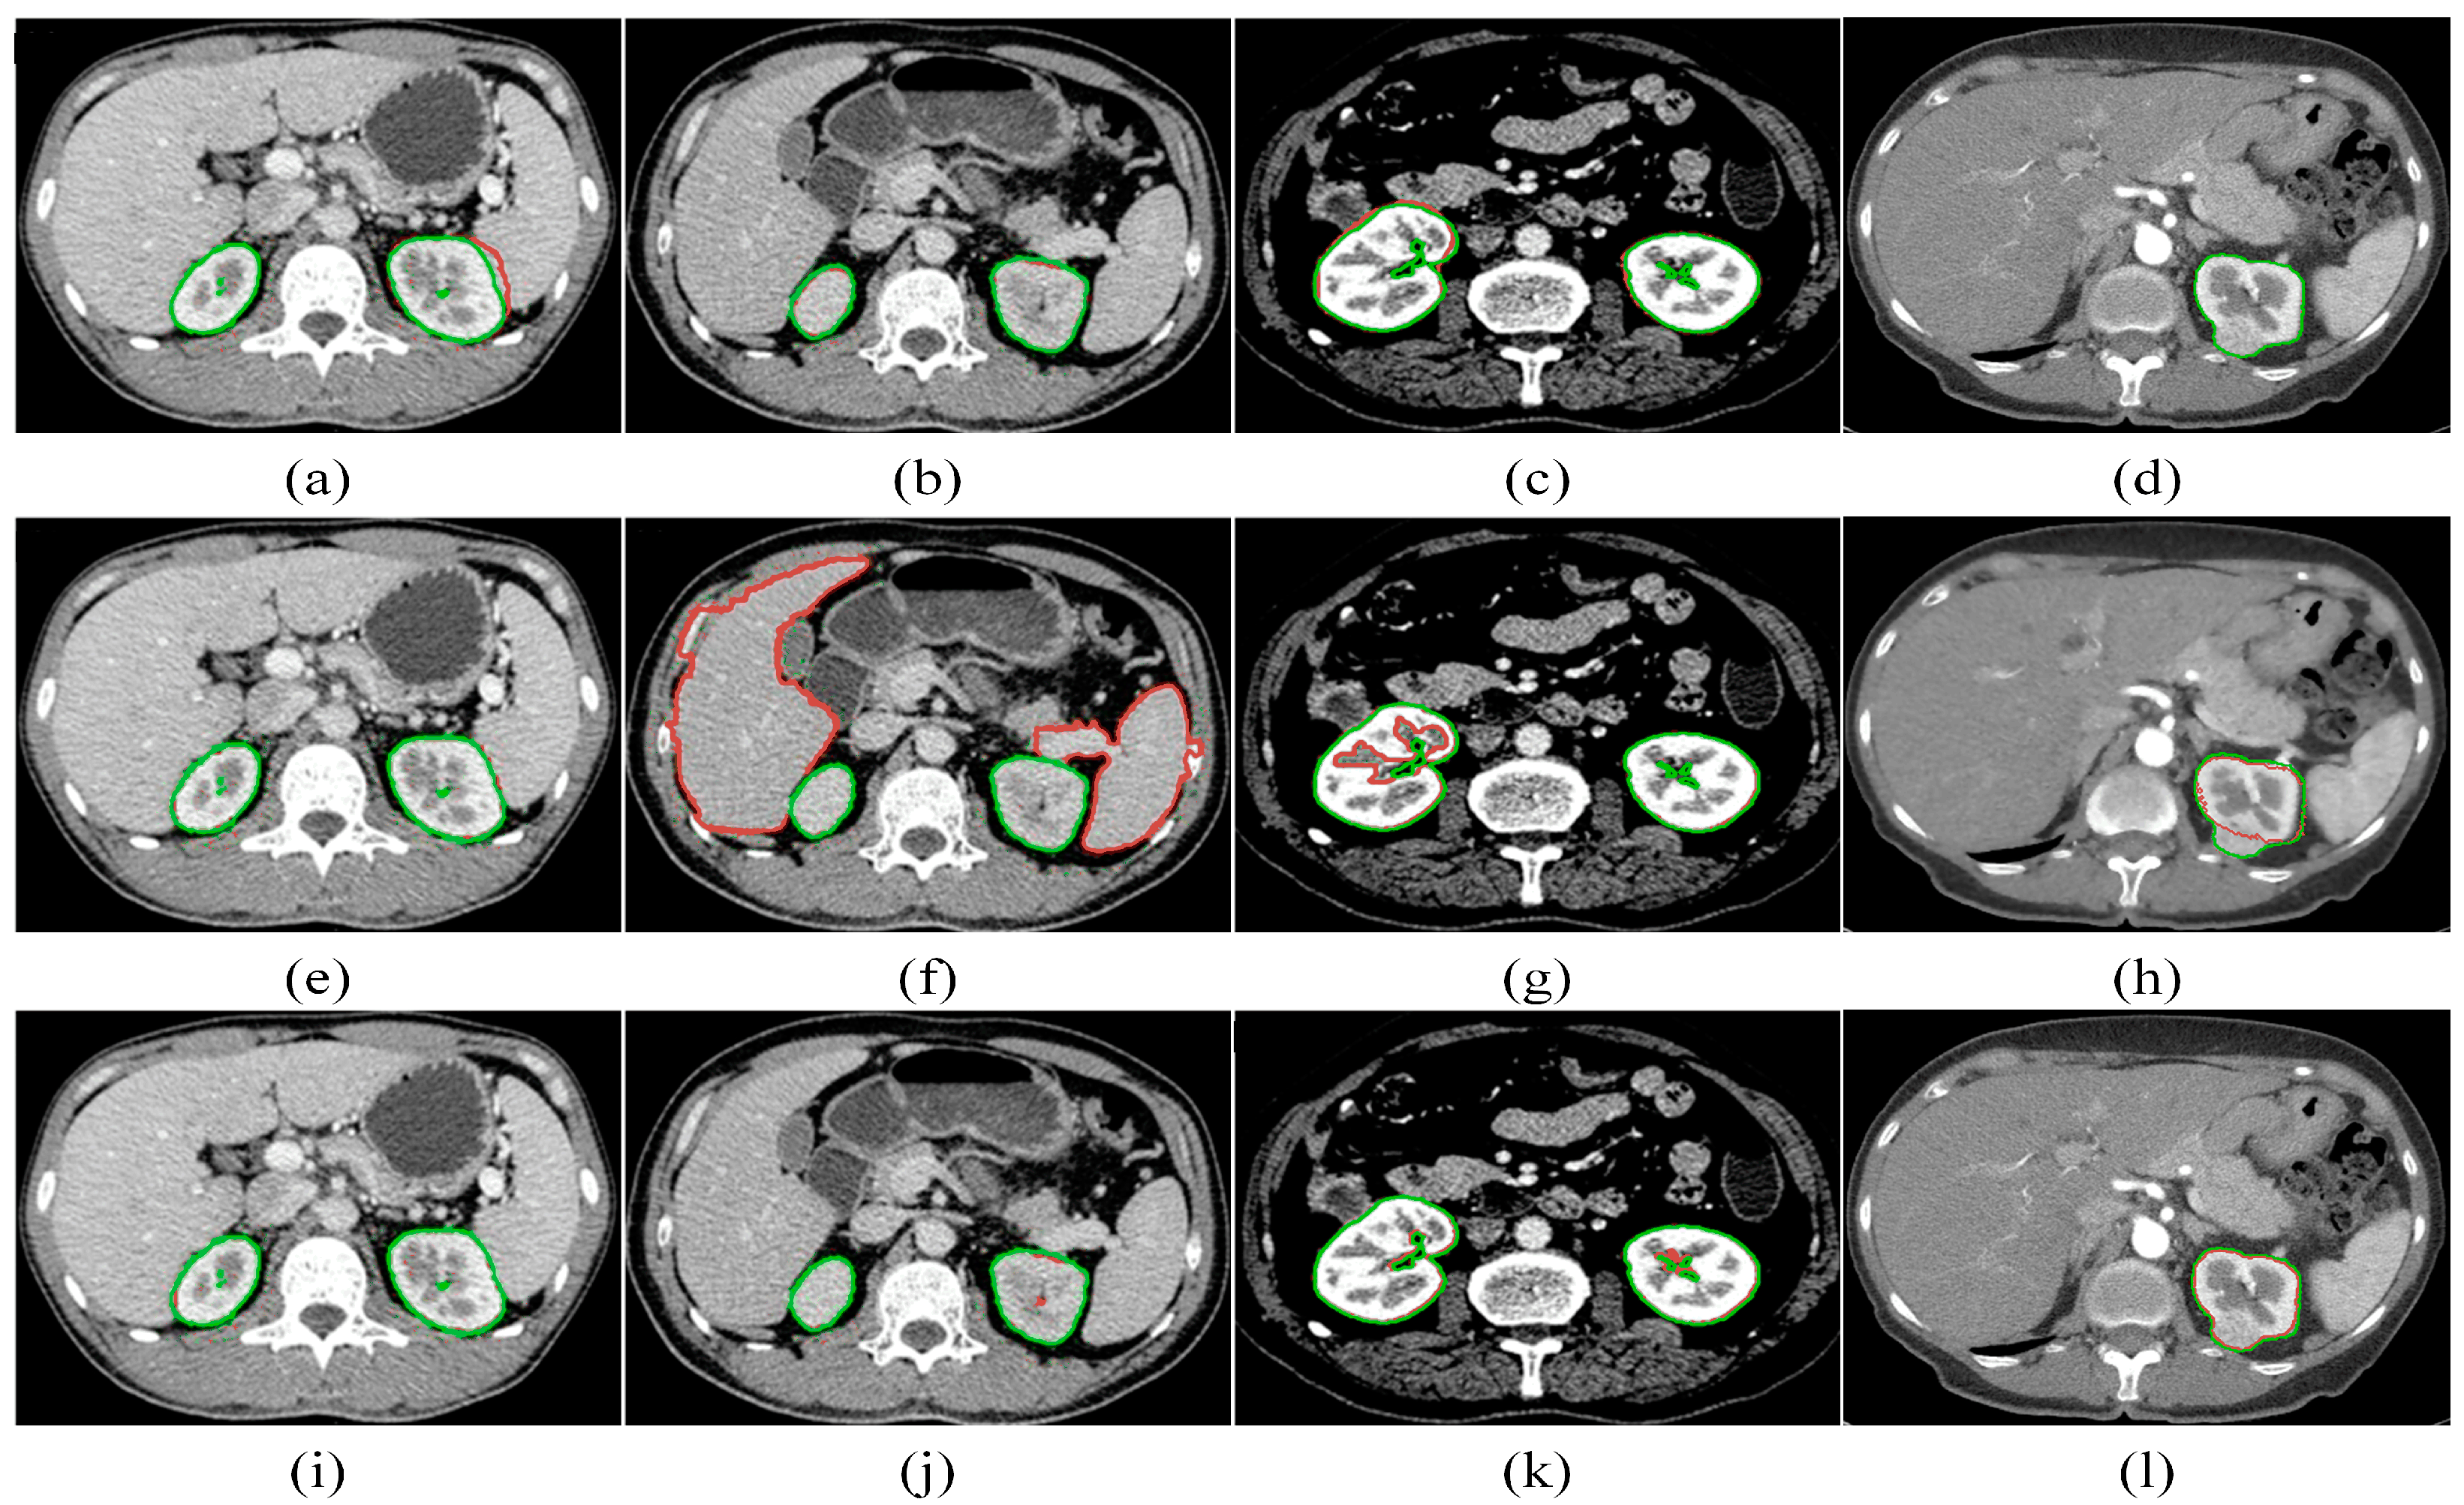

To demonstrate the high performance of our kidney segmentation framework, we compare our proposed method with the multi-atlas [35] and kernel graph cuts (KGCs) [36]. For the KGC experiment, the K-Means cluster result is utilized to construct the graph and perform the postprocessing of the filling operation to achieve the best possible results. Figure 14 depicts the kidney segmentation results of four kidneys, where the three rows indicate the corresponding segmentation results of the multi-atlas method, the KGC method, and the proposed method, respectively. The manual ground truth is shown in green, while the segmentation result is in red. From Figure 14a, it can be observed that the multi-atlas method fails to segment the right kidney and the right kidney is over-segmented. The KGC method, as seen from the results, has over- or under-segmentation problems. Additionally, it could not handle low-contrast images, as demonstrated in Figure 14f, and the intensity inhomogeneity of kidneys, particularly the renal medulla, which is not surrounded by the cortex (see Figure 14g). For kidneys with tumors, the multi-atlas method fails to segment the entire kidney, as shown in Figure 14d, and the KGC method cannot segment the tumor part, as shown in Figure 14h. In comparison, our method accurately segments not only the healthy kidneys but also the tumors, as shown in Figure 14l. In comparison with the multi-atlas method and the KGC model, our proposed approach could segment kidneys accurately.

Figure 17 presents the visual comparison of the segmentation results between the proposed approach and some deep learning-based ones. It is evident from the figure that the performance of TotalSegmentator is relatively lower. While it shows strong performance on general datasets, our experiments indicate potential degradation on datasets not specifically tailored to its training. Other models exhibit varying degrees of over- or under-segmentation. Among these models, 3D UNet performs admirably by leveraging three-dimensional kidney features, although it shows limitations in delayed segmentation results. Our proposed method demonstrates strong capability in segmenting kidneys with varying locations, shapes, and sizes. The segmentation results produced by our method are much closer to the ground truth (GT) compared to those obtained by other networks.

Figure 14. Comparative segmentation results of four randomly chosen CT slices for the multi-atlas [34] (ad), the KGC [35] (eh), and the proposed approach (il). The segmentation result is shown in red, while the manual ground truth is shown in green.